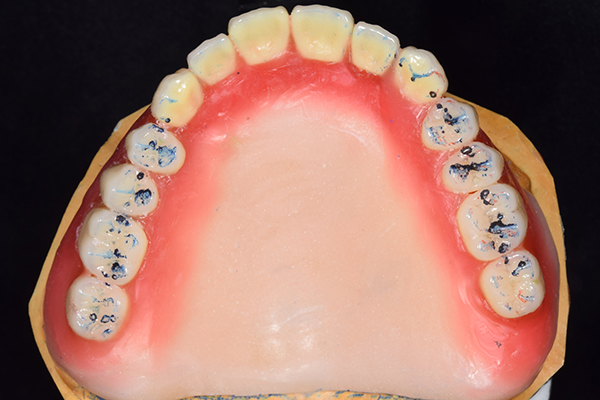

8.患者様のお口に入れて修正

この写真は、実際にお口の中にいれてみて、噛み合わせのチェックを行い、調整したものになります。 上下の入れ歯で青い点、赤い点がはっきりあり、これはしっかり奥歯で噛めるというサインになります。 また、入れ歯自体の大きさや、違和感が強くないか、お顔と調和しているか、唇との関係などをみていきます。もし、ここで大きな修正が発生する場合はもう一度お時間をもらって次回再度確認させて頂きます。 これで修正が終わったら、その模型を技工所に送り、入れ歯を完成させてもらいます。